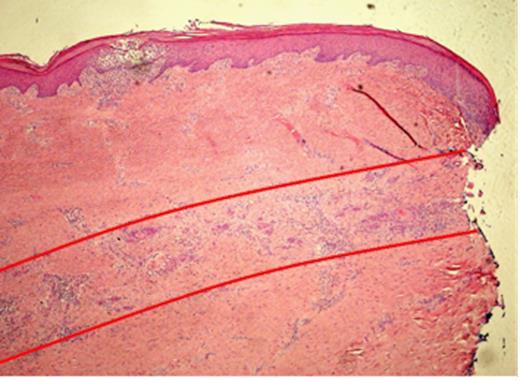

Histopathological slide of the indurated skin taken 10mm away from the ulcer showing a moderately differentiated Squamous Cell Carcinoma invading the deep dermis in a band like fashion, parallel to the epidermis (red lines). The local infiltration is well confined to the subcutaneous plane without peri-neural or deep structure involvement

Pathological examination of the plantar fascia revealed extensive invasion of the subcutis, extending radially for up to 15mm beyond the area of ulceration (Fig. 1). The tumour was 6mm thick and confined to the subcutaneous plane, well clear of the underlying muscle and bone. Microscopic examination of indurated areas revealed a moderately differentiated SCC invading the deep dermis in a band-like fashion parallel to the epidermis without evidence of peri-neural or deep structure involvement (Fig. 3).